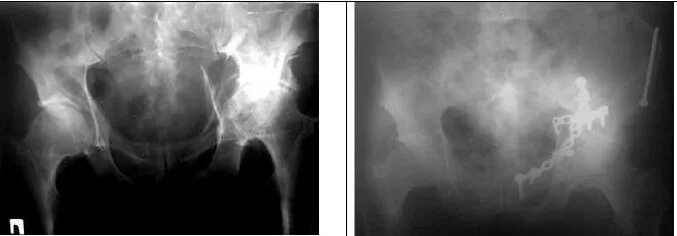

Перелом тазобедренной впадины